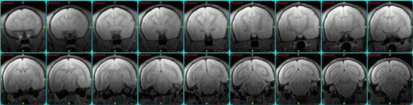

fMRI、Resting state fMRIの例

小動物のfMRI

ラットのDMN(Default Mode Network)の画像